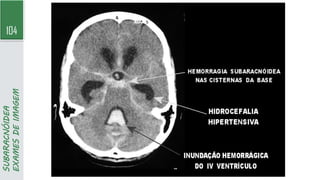

SUBARACNÓIDEA

A. HSA espessa difusa é observada na fissura inter-hemisférica anterior e nas fissuras sylvianas bilaterais, além da cisterna quadrigeminal. Identificou-se um aneurisma na

artéria cerebral média esquerda

B. HSA perimesencefálica; identifica-se apenas um pequeno foco de sangue na cisterna interpeduncular